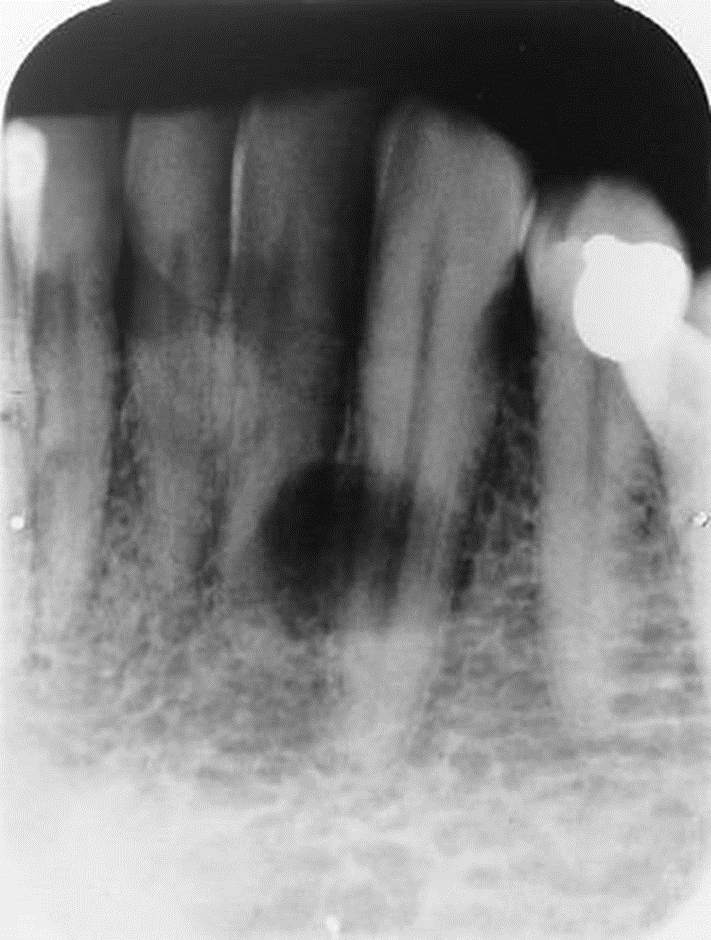

1. Mary is a 67-year-old who was referred to the periodontist. As part of the adiographic examination, this small radiolucent lesion was detected. The teeth were vital. Considering the patient’s age and the location, size, and clinical findings, what is your diagnostic impression?